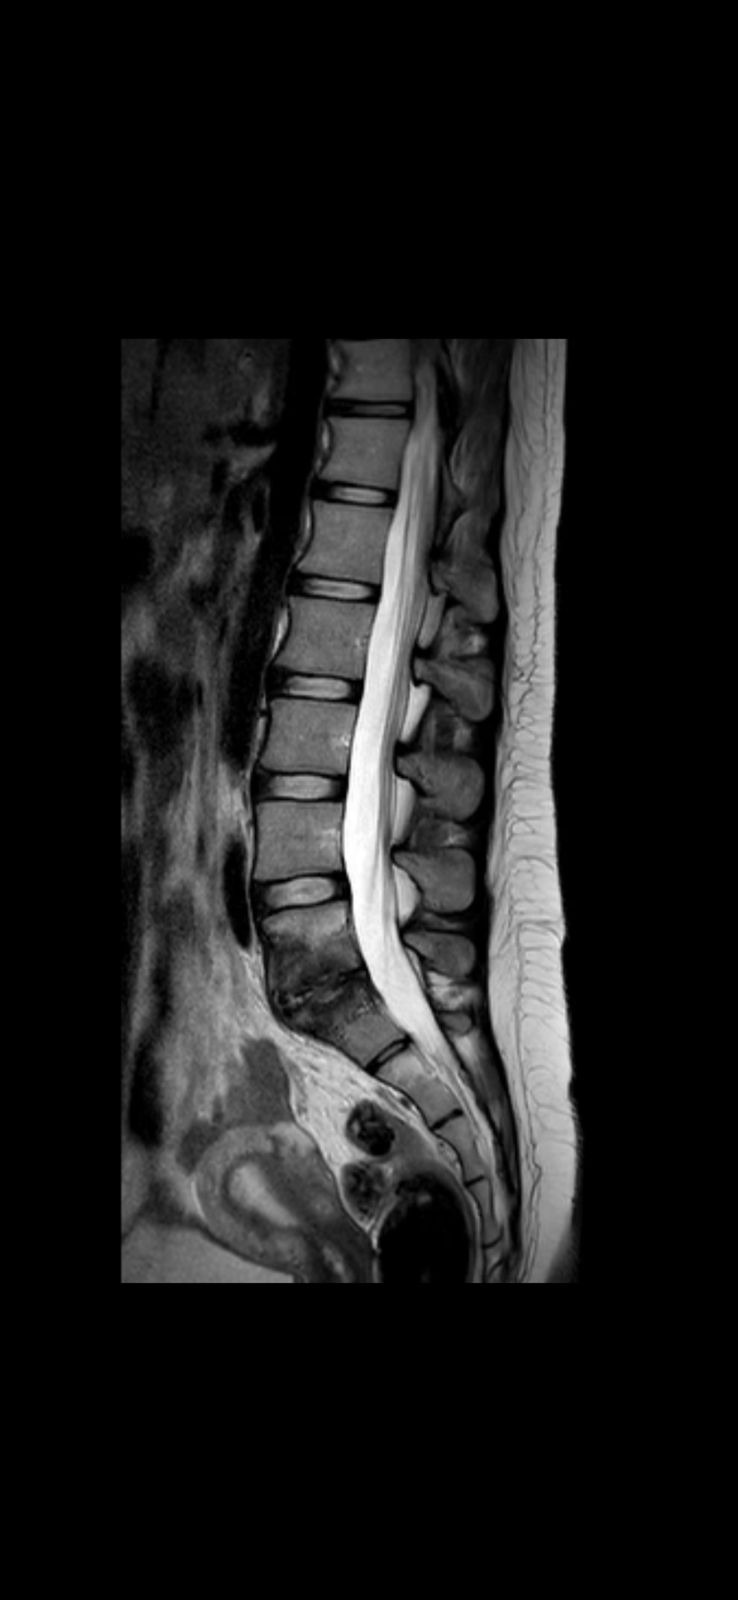

Tengo una infección en la columna, específicamente en L5-S1, que está destruyendo mi hueso. Los médicos necesitan operarme para lijar el hueso infectado y detener el daño. Si no me operan cuanto antes, esto puede empeorar y dejarme con secuelas permanentes.